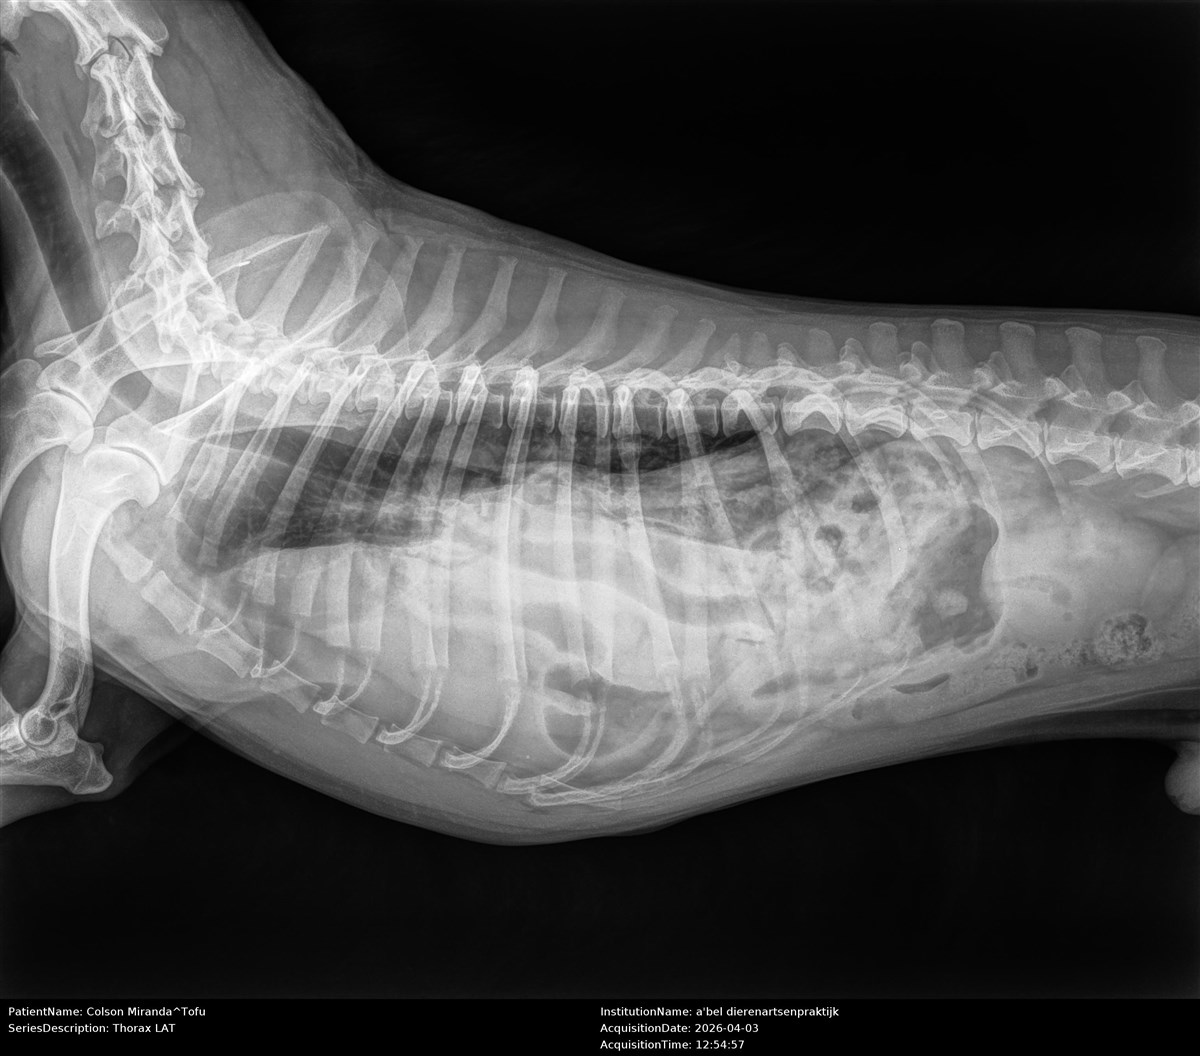

Een 2 weken geleden ontdekten we dat Toffu mogelijk geboren is met een diafragmatische hernia. Dit betekent dat zijn milt, darmen, lever en maag in zijn borstkas zitten, waardoor zijn longen en hart constant onder druk staan.